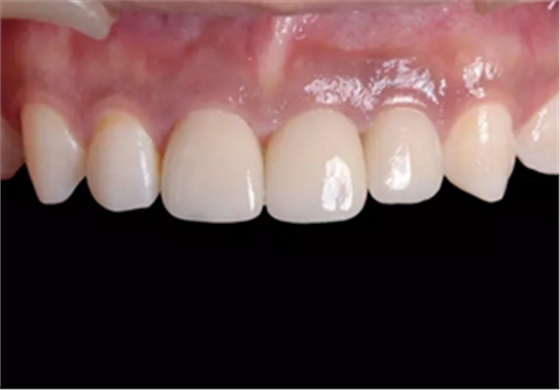

图23 最终修复后即刻口内像

图25 最终修复后复查口内像

(4)最终修复。种植体周围软组织改建成熟以后,进行最终修复。本 病例采用两步法印模技术精确记录种植体的三维位置和种植体周围软组织穿 龈轮廓外形。 首先,口内制取临时冠及周围软硬组织的硅橡胶阴模,复制软硬组织 表面形态。然后,取下临时修复体,常规制取闭窗式种植体水平聚醚印模, 精确记录种植体的三维位置,灌制含人工牙龈的超硬石膏模型。最后,去除 模型上的人工牙龈,将临时修复体戴入到模型上,在临时修复体周围和硅橡 胶阴模内注入人工牙龈,将阴模就位到含临时冠的石膏模型上,精确转移穿龈轮廓外形,获得工作模型。 制作螺丝固位的一体化氧化锆基台冠,以切削方式制作完成后,表面 添加饰瓷来获得理想的美观效果。 术后7个月,戴入最终修复体,红白美学效果满意。

(5)复查。种植体周围骨水平稳定,龈乳头及龈高点位置稳定,龈缘 曲线形态理想,唇侧软硬轮廓良好,功能满意,修复效果符合预期。